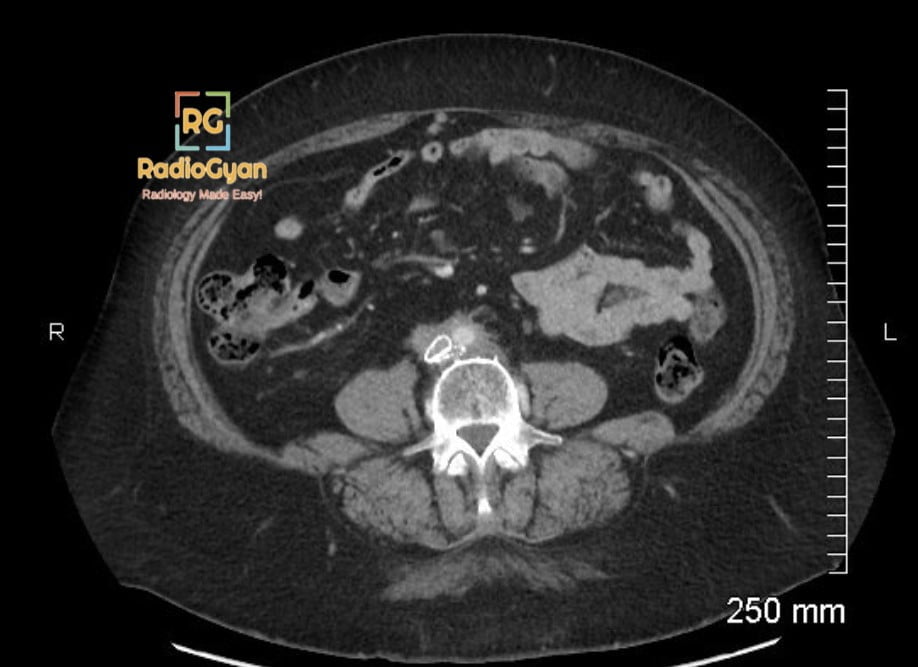

Maiden waist deformity is caused by medial deviation of both ureters due to retroperitoneal fibrosis, a condition characterized by abnormal proliferation of fibrous tissue in the retroperitoneal space. This fibrotic process commonly involves the ureters at the level of the lumbosacral junction, leading to their medial displacement and often resulting in ureteral obstruction.

The sign is named โmaiden waistโ because the medial indrawing of both ureters produces an appearance resembling the narrow waist of a maiden, reflecting the characteristic shape formed by the converging ureters on imaging.

Fibrous tissue proliferation in the retroperitoneum selectively encases and contracts around the ureters, pulling them medially and causing a focal narrowing or โwaistingโ in their course. This mechanical effect leads to the characteristic medial deviation visible on imaging studies such as intravenous urography, CT urography, or MRI.